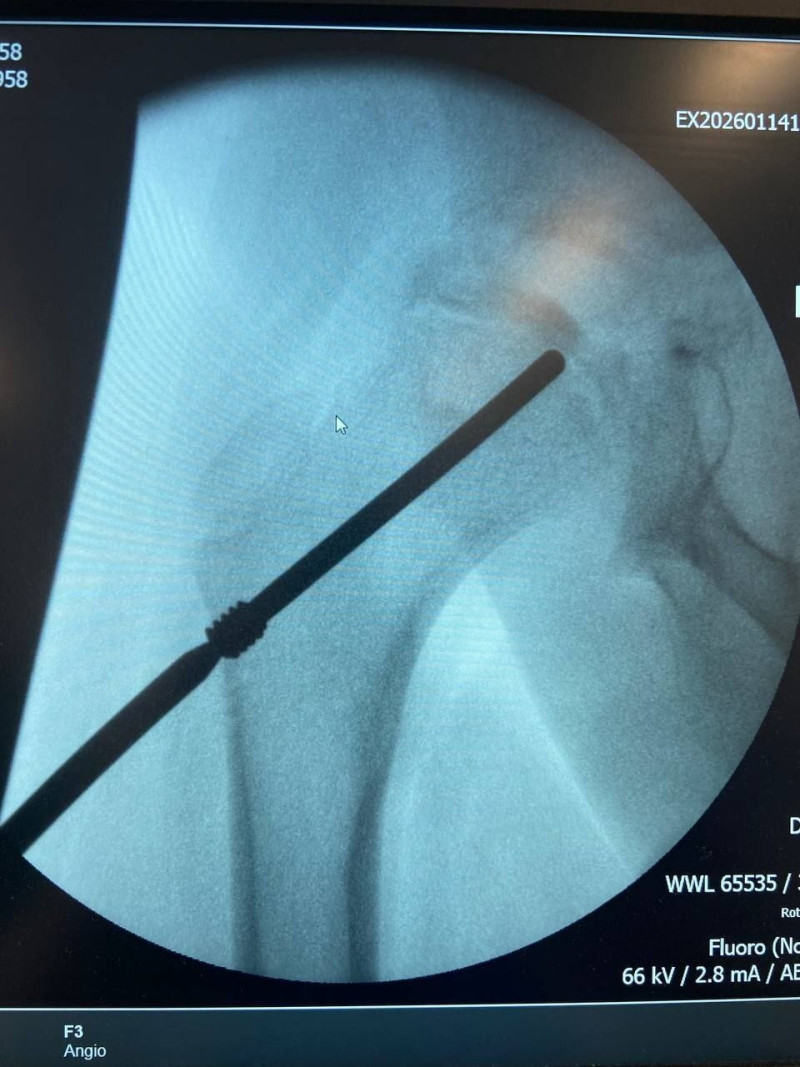

Специалисты Самарской областной детской клинической больницы имени Н.Н.Ивановой впервые выполнили операцию по имплантации инновационного медицинского устройства — ортопедического электрета.

Уникальная операция проведена 9-летнему мальчику с болезнью Легга-Кальве-Пертеса. Это тяжелое инвалидизирующее заболевание, приводящее к асептическому некрозу головки бедренной кости. У ребенка были такие симптомы как хромота и боль. Традиционное лечение таких заболеваний предполагает многолетнюю (до 5 лет) разгрузку сустава с использованием костылей, иммобилизацию или сложные операции.

✔️"Имплантация инновационного устройства, приобретенного для ребенка при содействии благотворительного фонда и министерства здравоохранения региона, должен уменьшить продолжительность заболевания и, как следствие, снизить тяжесть течения патологического процесса" - рассказал главный внештатный детский травматолог-ортопед министерства здравоохранения Самарской области, врач-травматолог-ортопед детской больницы имени Ивановой Павел Рыжов. - Ортопедический электрет — это российская разработка, представляющая собой имплантируемое устройство для постоянной электростимуляции процессов в костной и хрящевой ткани. Имплантат создает вокруг пораженного сустава постоянное электрическое поле, которое активирует естественные восстановительные механизмы организма, уменьшает воспаление и отек. Это способствует сокращению сроков лечения".